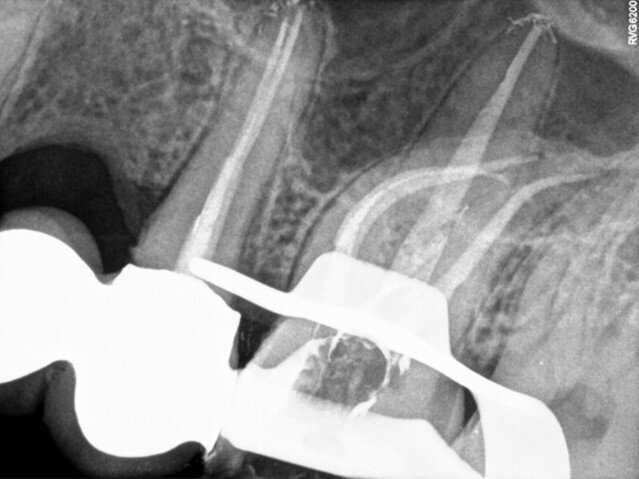

I decided on single-visit endodontic treatment. The treatment began with administration of local anaesthetic and dental dam isolation. Crown access was performed with a diamond bur and ultrasonic tip (CAVI 2-D, VDW), which was also used to perform the removal of the coronal portion of the pulp and canal localisation. On access, four canals were identified by inspection with an endodontic probe. The working length of the palatal canal was 21.5 mm (C-PILOT, ISO size 10, VDW), of the mesiobuccal and distobuccal canal was 21.0 mm (C-PILOT, ISO size 10), and of the second mesiobuccal canal was 20.0 mm (C-PILOT, ISO size 8). An electronic apex locator was used for working length confirmation. As can be seen in the panoramic radiograph and dental radiograph (Fig. 2), the canals were quite narrow and curved, so I decided to use rotary files (VDW.ROTATE, VDW).